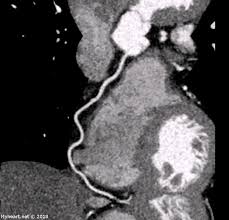

Ct Scan In Er Ct Scan Machine

Ct Scan In Er Ct Scan Machine from www.researchgate.net